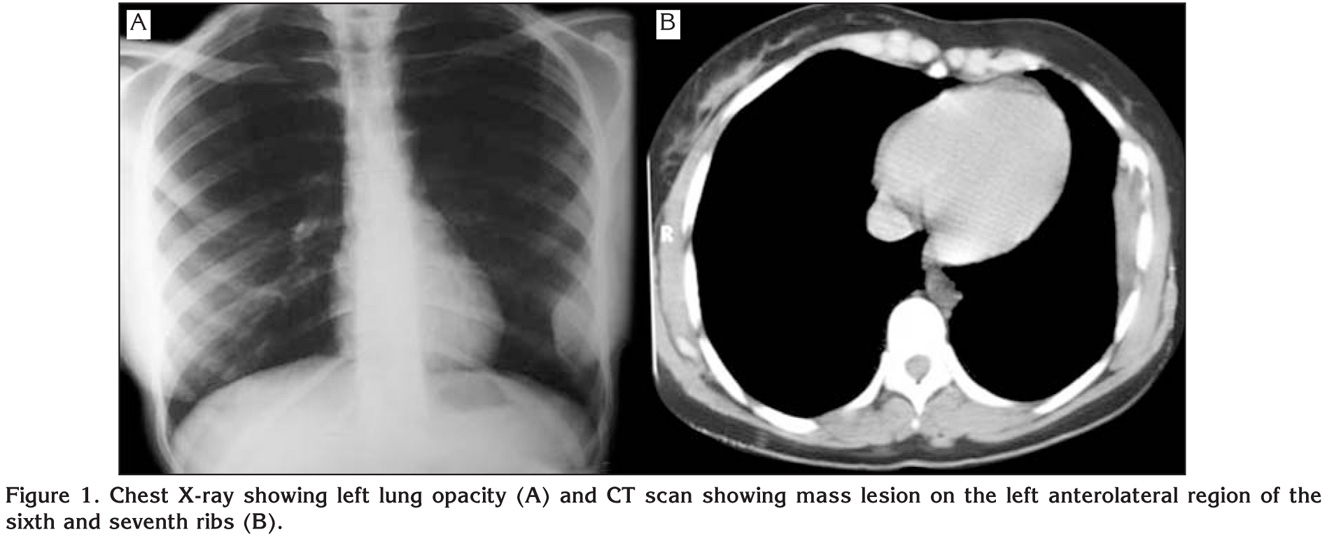

A 28-year-old woman presented with pain on her left side for three months. On physical examination, pain was present with palpation on the left side of chest wall and lung sounds were normal. Laboratory examinations were unremarkable. Postero-anterior chest X-ray showed opacity on the left sixth and seventh ribs. The patient admitted to our clinic with thorax computed tomography (CT) and PET/CT (positron emission tomography/computed tomography). CT of the thorax revealed an ill-defined destructive mass on the left anterolateral region of the sixth and seventh ribs (Figure 1). PET with 18 F-FDG depicted the lesion as a low grade malign neoplasm (SUVmax: 4.5) without any metastasis. We thought that the lesion was malignant according to the clinical and radiological findings. Because of the pain, we did not prefer taking biopsy under local anesthesia; we did it under general anesthesia. We studied frozen from the soft parts of the tissue which was taken with incisional biopsy. It was reported as malignant mesenchymal tumor or osteosarcoma. She underwent left posterolateral thoracotomy and a moderate swelling through the inside of left hemithorax originated especially from the sixth rib was detected. The sixth and the seventh ribs were enblock resected. Histopathological examination revealed the neoplastic cells that were uniformly small with diffuse growing pattern. These cells were strongly stained with focal SMA (smooth muscle actin) areas with vimentin. Tumor cells were negative for CD45, CD99, CD33 and CD56. Also chromogranin, pancreatin, EMA, TTF-1 were all negative. In addition to these findings, the most important component was osteoid production especially on the invaded regions (Figure 2). According to these clinical and histopathological findings the case was reported as primary SCO of the ribs. She was discharged on the 7th day of operation without any complication and referred to the medical oncology unit for chemotherapy. She was healthy and disease-free on the 17th month of follow-up (Figure 3).

Figure 1